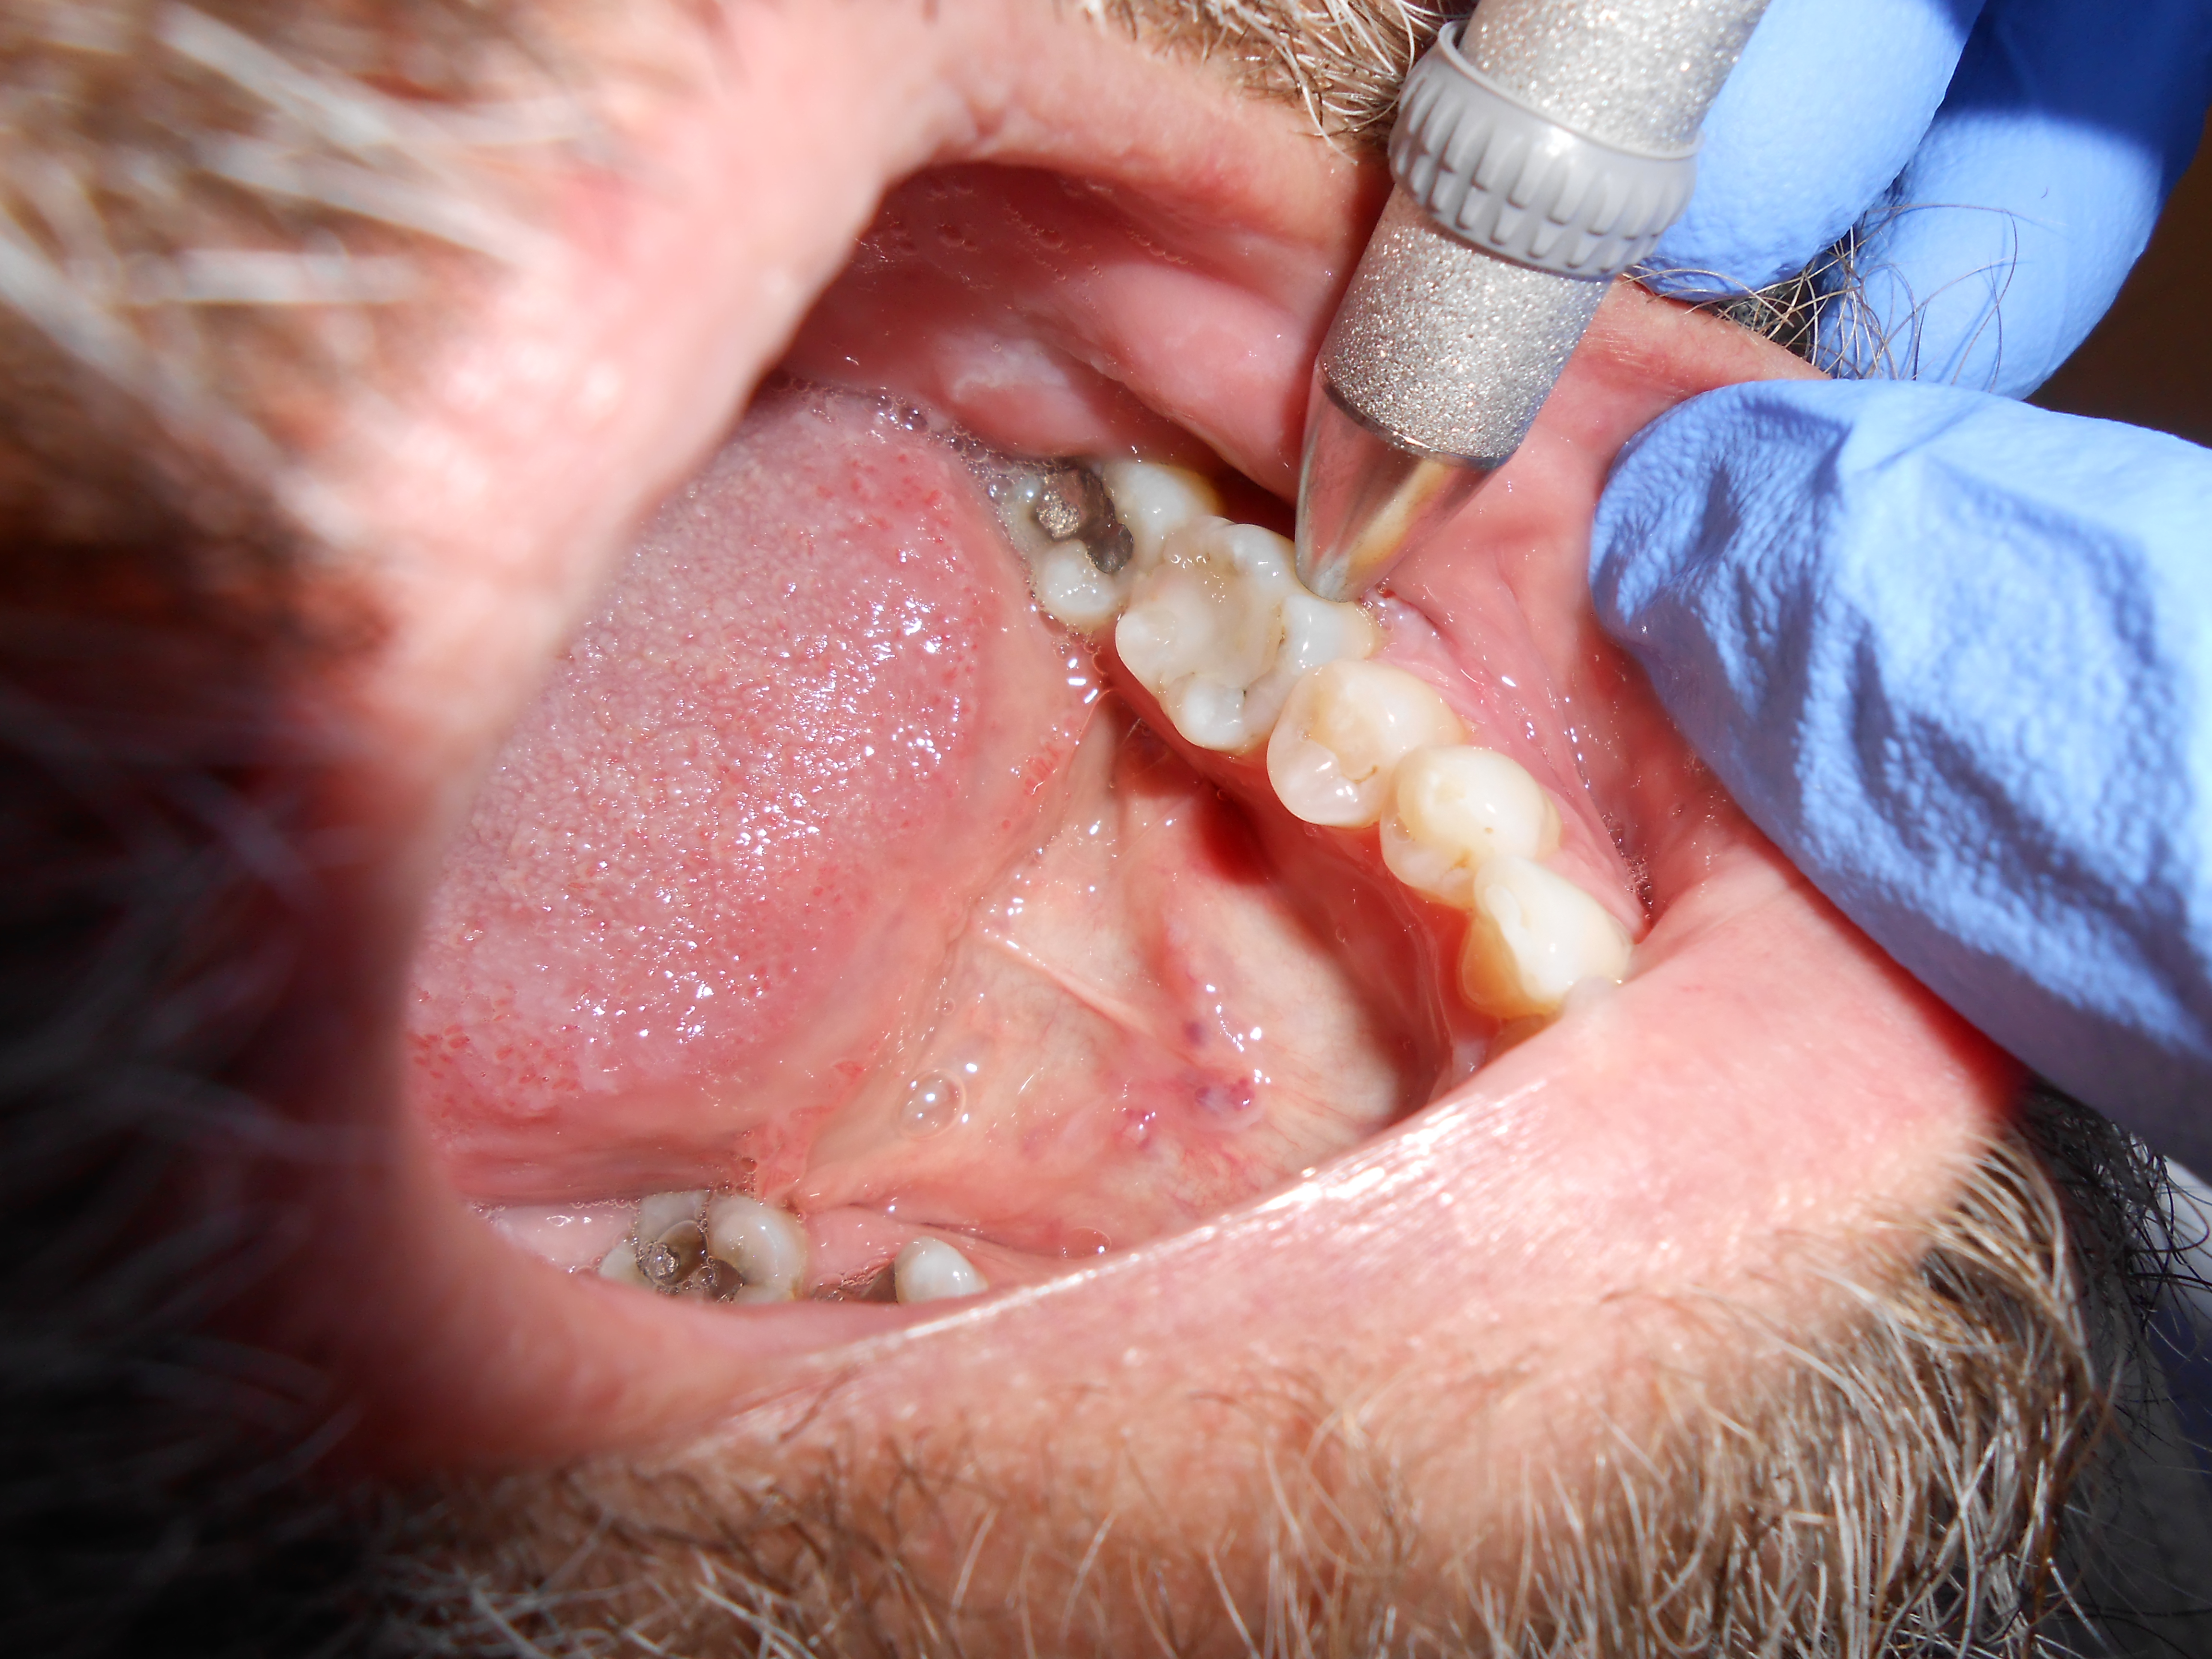

Chronic apical abscess is typically indicated by a radiograph that reveals a radiolucency. Clinically, there is a sinus tract present on the gingival tissue. It is paramount that the draining sinus tract be traced with a gutta-percha cone and then radiographed (Figure 3 and Figure 4).

Clinical confirmation of the periradicular diagnosis—chronic apical abscess on tooth No. 19. The tooth is not sensitive to percussion or palpation. A gutta-percha #25/.04 cone is inserted into the sinus tract.

Figure 3